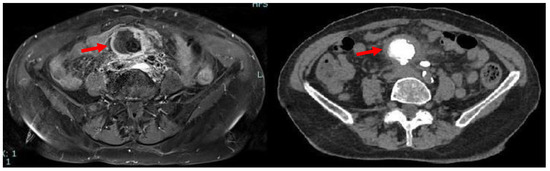

Due to iodinated contrast agent allergy, the patient underwent abdominal contrast-enhanced magnetic resonance imaging (CE-MRI) scan complete with computed tomography (CT) scans documenting, in the hypogastrium, the presence of voluminous multilobular lymphadenopathies (about 45 mm of maximum diameter) with calcific nucleus surrounding the mesenteric vessels and infiltrating the mesenteric fat (Figure 1).

Figure 1.

Axial MRI (left) and CT (right) scan showing the presence, in mesogastrium, of a nodular mass (red arrows) with contrast enhancement at MRI and internal calcifications at CT.